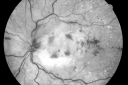

87-year-old woman I saw in the office on February 8, 2008. She has had age-related macular degeneration in both eyes for some time with disciform scars. She takes a baby aspirin about every other day. She has noticed over the last month or two decreased vision in her left eye. She also has had borderline glaucoma for some time.

VISUAL ACUITY: OD: 20/200, OS 20/400. IOP: OU 19.

OD: Vertical C/D ratio is 0.3. There is an atrophic macular scar 3 disc diameters across.

OS: Vertical C/D ratio is 0.1. There is 3+ optic nerve edema. There is a posterior vitreous separation. There is an atrophic macular scar 3 disc diameters across. There is also dilated retinal veins in all four quadrants with retinal hemorrhage in all four quadrants.

OCT SCAN: The OCT scan of the right eye shows retinal atrophy. The left eye shows retinal atrophy with macular edema predominately nasal to the fovea.

FLUORESCEIN ANGIOGRAM: FA of the left eye shows poor circulation with the re-circulation time of almost 20 seconds, which normal being less than 4 seconds. In the left eye there is also late leakage from the macular vessels. The perfusion in the periphery looks pretty good. I do not see greater than 10 areas of non-perfusion. The right eye has hyperfluorescence corresponding to the macular scar.

1. AGE-RELATED MACULAR DEGENERATION – BOTH EYES

2. CHRONIC MACULAR SCARS – BOTH EYES

3. NEW CENTRAL RETINAL VEIN OCCLUSION WITH MACULAR EDEMA AND OPTIC NERVE EDEMA – LEFT EYE